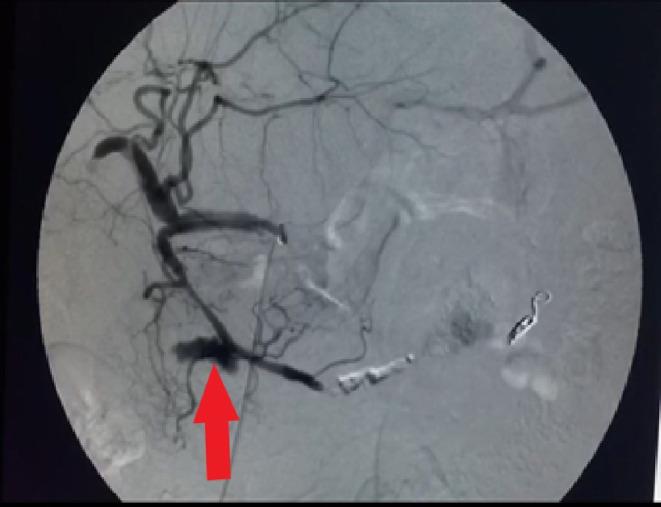

A 55-year-old woman with a history of coronary artery disease was referred to our hospital with abdominal pain as her primary complaint. Early works revealed anemia, a small amount of free peritoneal fluid, and a possible large aneurysm or pseudoaneurysm by the greater curvature of the stomach. She underwent emergency angiography that showed a large aneurism/pseudoaneurysm of the gastroepiploic artery. Successful embolization of the lesion was performed using the isolation technique. Perforation of a side branch of the gastroduodenal artery was observed on the immediate postembolization control angiography. Therefore, parent artery coiling was done immediately with good results. She was symptom-free and stable hemodynamically after the procedure, during the hospital course, and in the follow-ups.

一名有冠状动脉疾病史的55岁女性因腹痛为主诉被转诊至我院。早期检查发现贫血、少量腹腔游离液体,胃大弯处可能存在大动脉瘤或假性动脉瘤。她接受了急诊血管造影,显示胃网膜动脉有一个大动脉瘤/假性动脉瘤。采用隔离技术成功栓塞了该病变。栓塞后即刻控制血管造影观察到胃十二指肠动脉一分支穿孔。因此,立即对供血动脉进行了弹簧圈栓塞,效果良好。术后、住院期间及随访过程中她均无症状且血流动力学稳定。